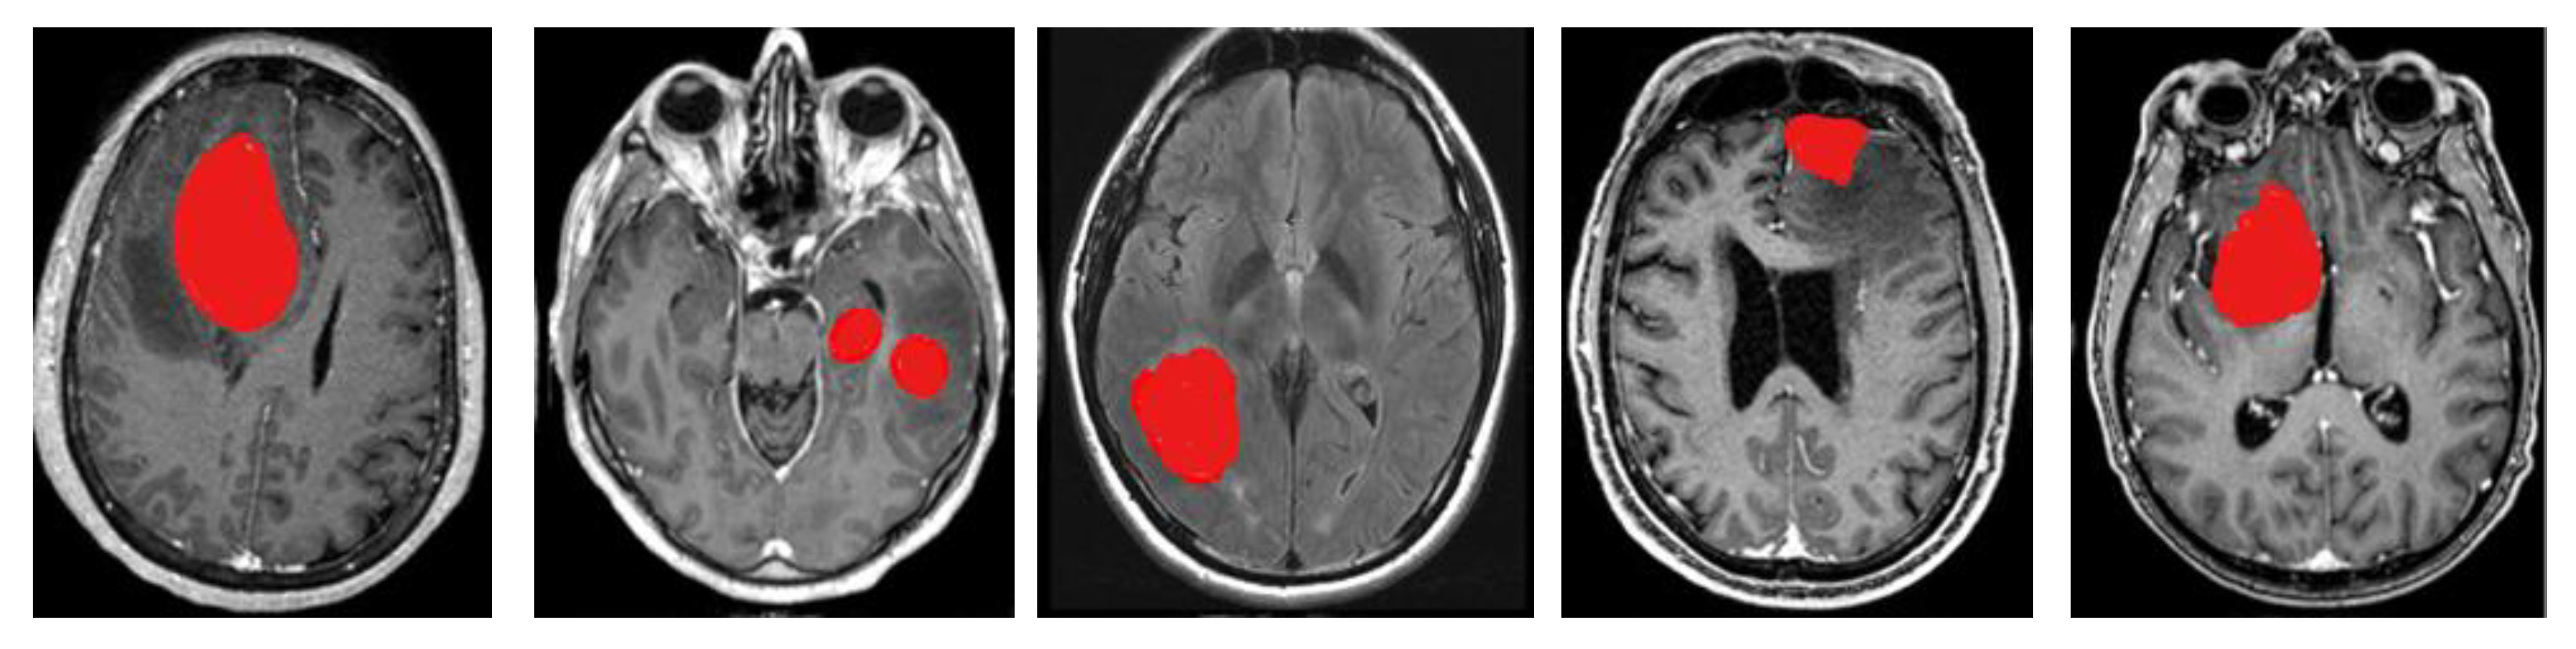

This is the final modified form of the Canny Mayfly equation. Next, the findings that were acquired from this step are sent on to the process of feature extraction. During this stage, the redundant information is removed so that the classification results can be improved. The segmentation results are shown in Figure 3.

Figure 3.

Segmentation results.